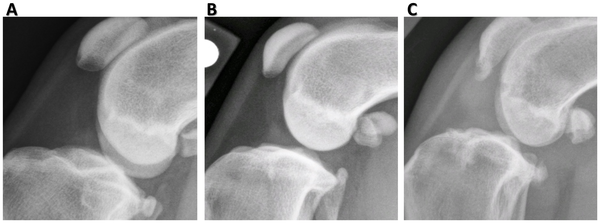

즉, 소형견에서 슬개골탈구보다 십자인대 단열이 무릎의 관절염을 더 더 심하게 유발한다라는것이다.

십자인대 단열은 슬개골 탈구보다 훨씬 빨리 교정해주는것이 옳다고 보아야 한다.

관절낭이 종창된것만으로도 십자인대의 이상을 추정할 수 있으니 되도록이면 최대한 빨리 치료를 해주는게 추천된다.